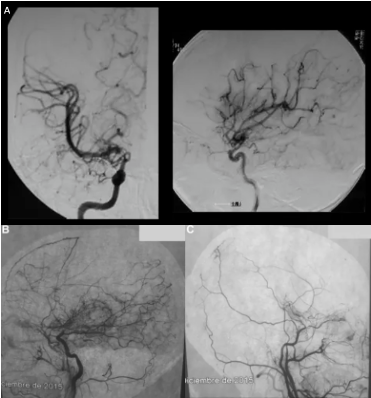

05INC巴特朗菲教授脑干手术成功经验

巴特朗菲教授有很多经验。他将根据脑干海绵状血管瘤的具体位置、大小和生长特征选择不同的开颅入口。通过脑膜、小脑和四个大脑室进行细致而熟练的递进。较重要的是决定从脑干表面进入哪里,然后准确地找到炸弹,然后用较细致的动作将其移除,但它根本不会伤害脑干。

在巴教授300多例脑干海绵状血管瘤手术中,95%以上的患者可以在手术后同一天拔下气管插管,二天转出ICU恢复健康生活。